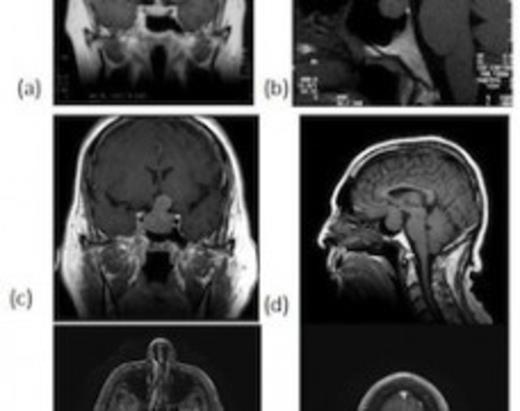

A 58-year-old gentleman was diagnosed with small cell lung cancer in 1995. He received local radiation and chemotherapy but was found to have recurrent disease confirmed by bronchoscopy in 2000. He was treated with additional chemotherapy and lobectomy. At recurrence MRI of the brain revealed a pituitary adenoma (Fig 1a,b) for which he elected observation.

MRI performed in 2000 revealing incidentally discovered pituitary tumor seen on coronal (a) and sagittal (b) views. MRI performed in 2008 revealing enlarging mass within the sella with suprasellar extension on coronal (c) and sagittal (d) views. Axial views reveal metastases in the cerebellum (e) and the parietal lobe (f)

In 2008, he presented with headaches and visual disturbance. Visual acuity was 20/25 in the right eye with complete temporal field defect, and 20/30 in the left eye with a shallow temporal field defect. Repeat MRI revealed enlargement of the sellar mass with extension into the cavernous sinus bilaterally and significant chiasmal compression. Also noted were three enhancing lesions within the brain suggestive of metastatic disease (Fig. 1c-f). CT of the chest, abdomen and pelvis demonstrated a mass involving the posterior aspect of the pancreatic neck. Laboratory evaluation revealed a prolactin level of 15.5ng/mL, growth hormone level of 0.3ng/mL, normal thyroid panel, and morning cortisol level of 1μg/dL.